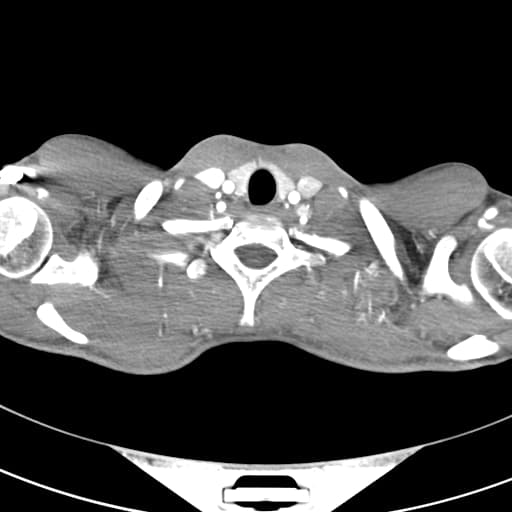

- Hình ảnh bốn buồng tim bình thường

- Bố trí song song của các động mạch lớn

- Động mạch chủ (Ao) xuất phát từ tâm thất phải (RV) và xuất hiện như một mạch dài

- Động mạch phổi (PA) xuất phát từ tâm thất trái (LV)

Trường hợp này cho thấy các hình ảnh điển hình của chuyển vị đại động mạch kiểu D (D-loop transposition of the great arteries).

Chuyển vị đại động mạch kiểu D - siêu âm tim thai (D-loop transposition of the great arteries - fetal echocardiogram)